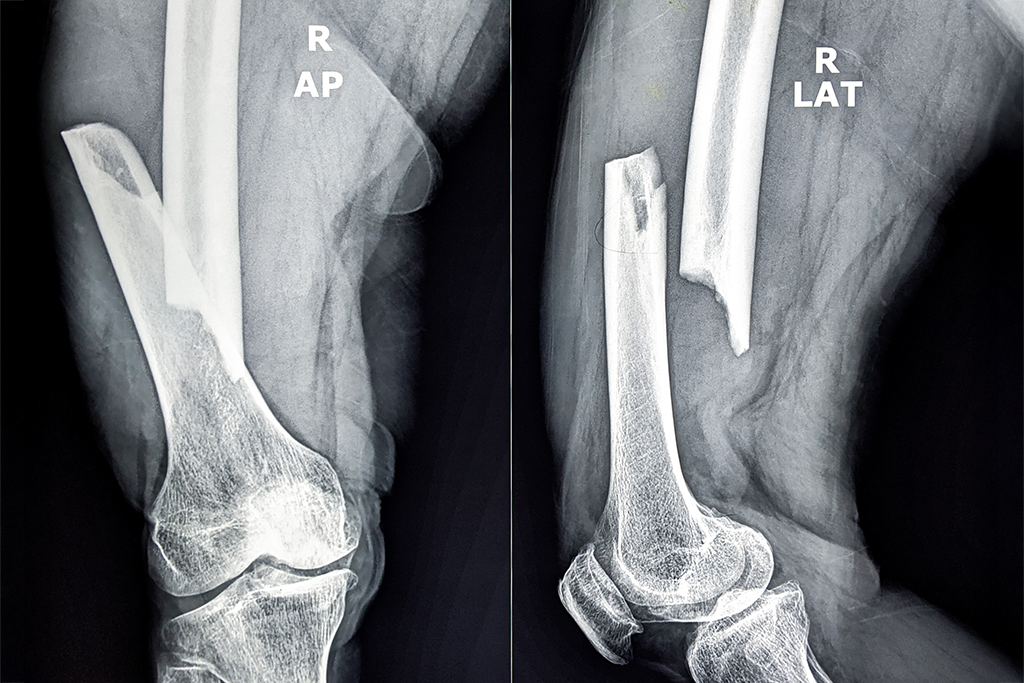

In cazul fracturilor instabile, deplasate sau care afecteaza articulatiile, interventia chirurgicala devine necesara pentru a reface alinierea corecta si stabilitatea osului.

Radiografiile, CT-ul sau RMN-ul sunt utilizate pentru a evalua cu precizie traiectul fracturii si eventualele complicatii. Imagistica 3D permite chirurgului ortoped sa planifice in detaliu interventia si sa aleaga cea mai potrivita metoda de fixare interna (placi, suruburi, tije).

In timpul interventiei, osul este realiniat si fixat folosind implanturi specializate care asigura stabilitate si favorizeaza o vindecare rapida si corecta. Tehnicile minim-invazive sunt preferate atunci cand este posibil, pentru a reduce trauma tisulara si perioada de recuperare.